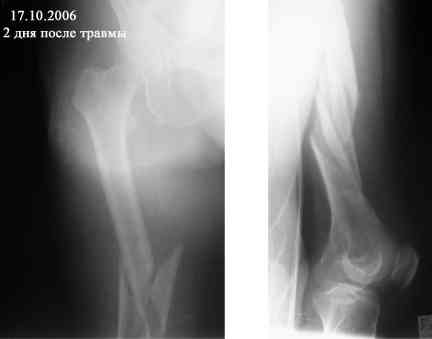

Представляю вашему вниманию снимки в динамике

Женщина 66 лет 15.10.2006 получила закрытый окольчатый перелом правой бедренной кости в с\з-н\з со смещением отломков. 17.10.2006 доставлена в травм.отделение (2-е суток лежала одна дома). При поступлении наложено скелетное вытяжение за бугристость большеберцовой кости - груз 5 кг, затем увеличен до 7 кг. Схематические рисунки контрольных Р-грамм прилагаются (прошу прощения за отсутствие Р-грамм, постараюсь "донести").В связи с отсутствием материальных средств и "удовлетворительным" положением отломков решено было скелетное вытяжение оставить как окончательный метод лечения. На 20.11.2006 отека правого бедра нет, пальпаторно умеренная болезненность в месте перелома, крепитации отломков нет (и по-видимому не было изначально),подвижность в месте перелома сохранена, но не выражена. Двигательных, чувствительных и трофических расстройств правой нижней конености нет. Уважаемые коллеги! Какова дальнейшая тактика в случае вероятной интерпозиции тканей? Больная "кровавое" оперативное лечение не "потянет" материально. Даст ли в данном случае что-то АВФ закрыто?